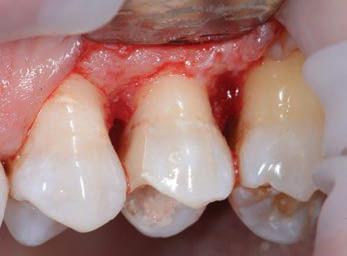

This element was not stimulated with the cold test and the radiographic image revealed an incomplete endodontic treatment (Figs. 1-2). The element seemed to present a suitable root length for a conservative restoration, but the apical position of the carious lesion and the proximity of the interdental bone ridge didn’t allow a correct rehabilitation with prosthetic crown, respecting the biological width.2

Figure 2: Initial radiograph showing endodontic dressing that had been present for some months, but the treatment was never completed. Note the depth of the caries lesion and the proximity of the interdental bone ridge, which may represent an obstacle for prosthetic rehabilitation.

Figure 1: Initial situation. The patient reported generic pain in the second quadrant, where there was a restoration in temporary material on tooth number 25.